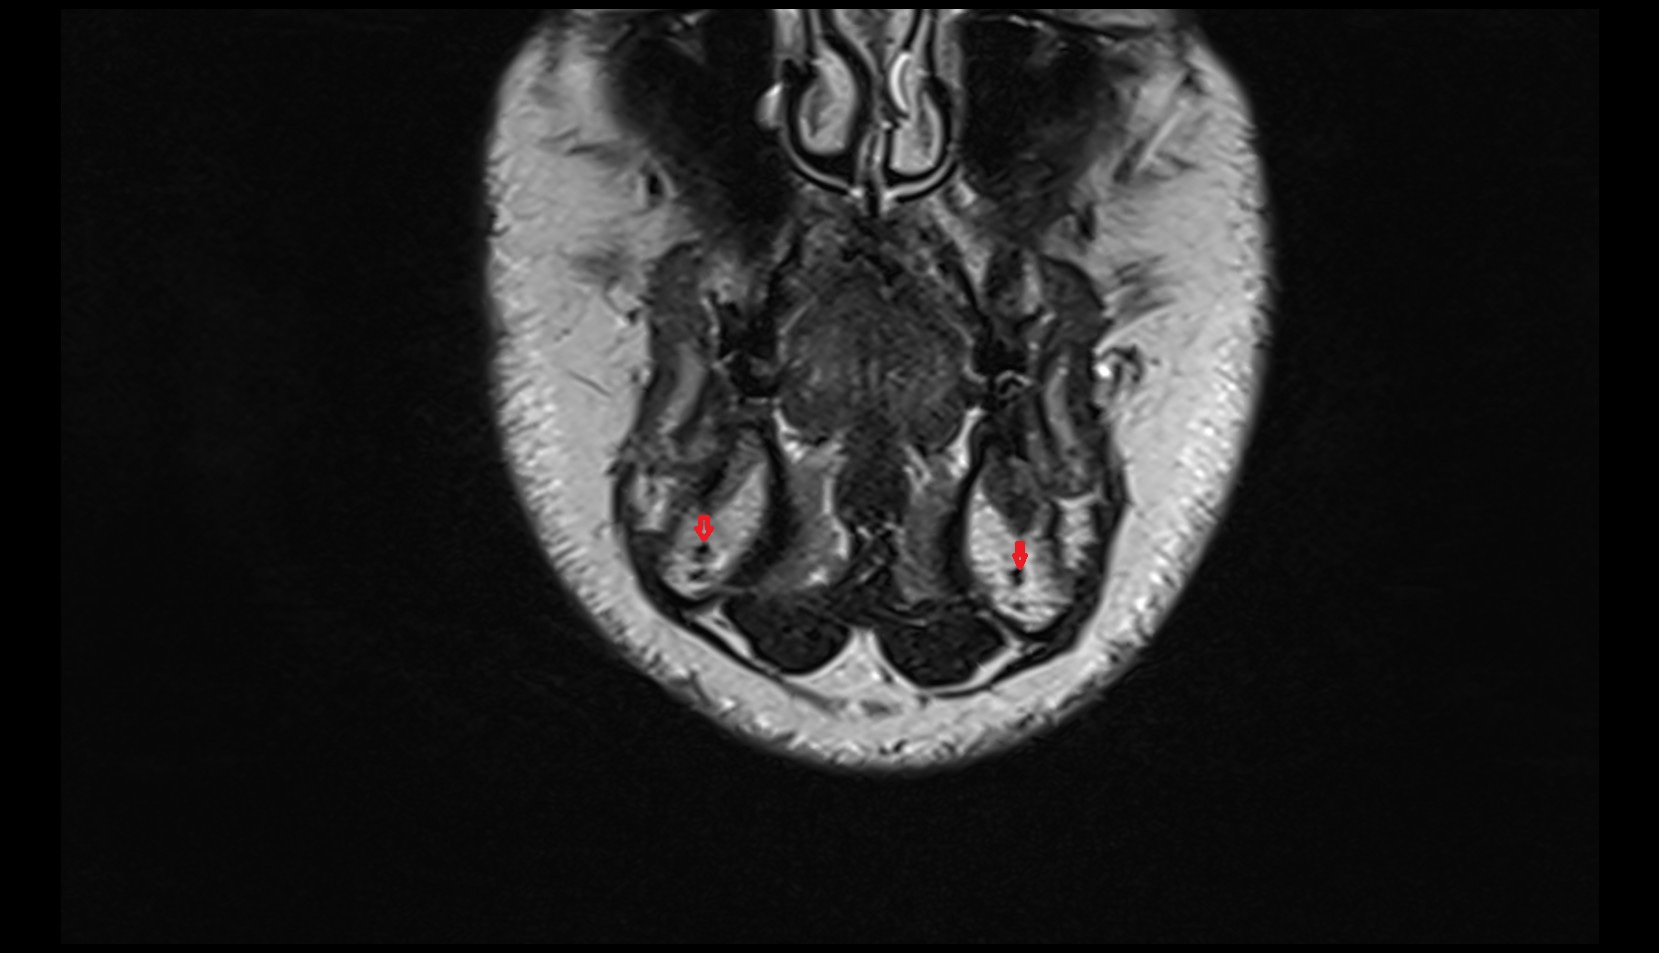

- Hippocampus